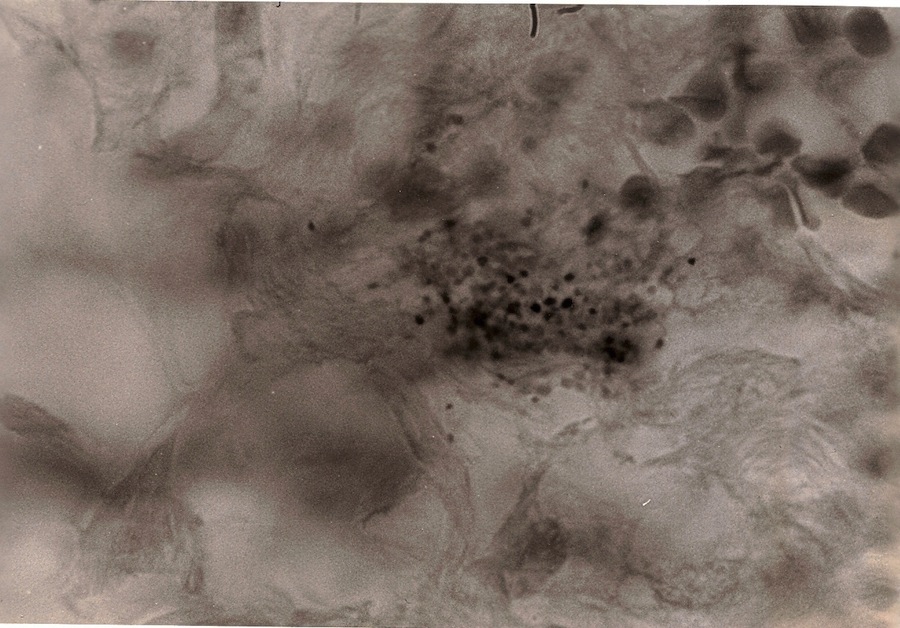

Dermatol Surg Oncol. 1981 Jun;7(6):483-91. Abstract In four cases of carcinoma of the breast, variably acid-fast coccoid forms were found in sections from their metastases to the skin and in one of these cases in sections of the primary carcinoma. In this one case, similar-appearing corcoid forms were observed within the sections of the primary malignancy. In this same case, Staphylococcus epidermidis was cultured and studied at once and as it aged for development of forms comparable to those found in the microscopic sections of the neoplastic process. The implications of the findings for etiology of carcinoma of the breast are discussed. |